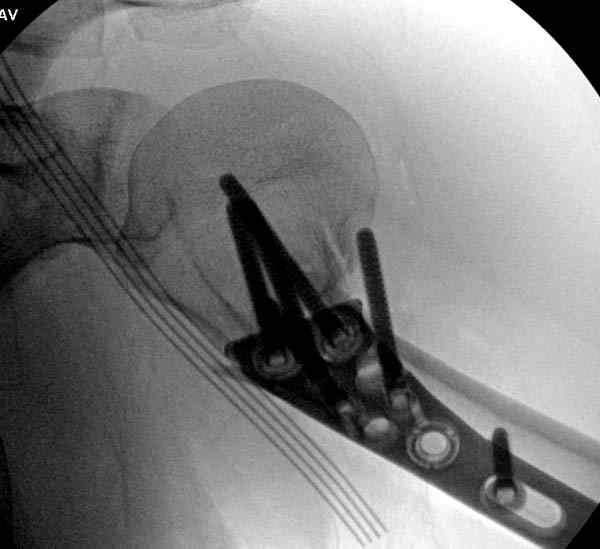

После устранения смещения пластина установлена выше (5,6,7) и финальные снимки (8,9,10)

Подбор импланта тоже имеет значение, например многие импланты направлены для фиксации перелома без учета ротаторной манжетки. Предпочтительными являются низко сидящие полиаксиальные пластины, где верхние шурупы можно проводить под углом в 120 градусов. (11)

Пластина от Synthes или ее копии (надеюсь простят критику друзья из Деоста) считаются трудным из-за обширности доступа, особенно при установке верхне-заднего шурупа, где доступ надо расширять в верхнем отделе до ротаторной манжетки. Верхне сидящие импланты предназначены для проведения опоры (buttress) за бугристость плеча, но тогда приходится сталкиваться с подакромиальным импинжментом.